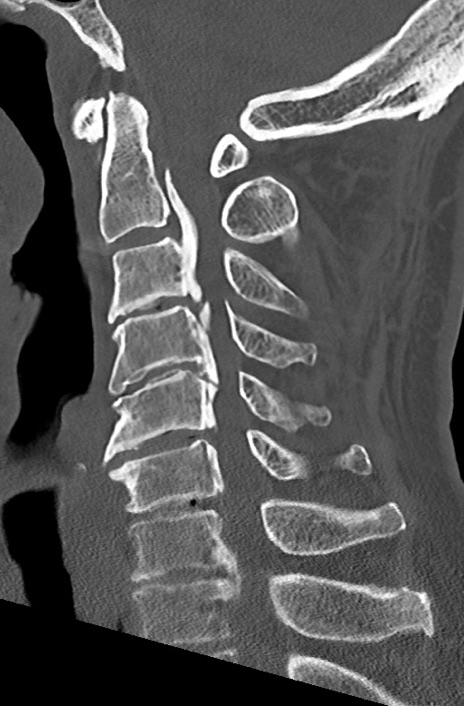

頚椎CT

矢状断像と横断像